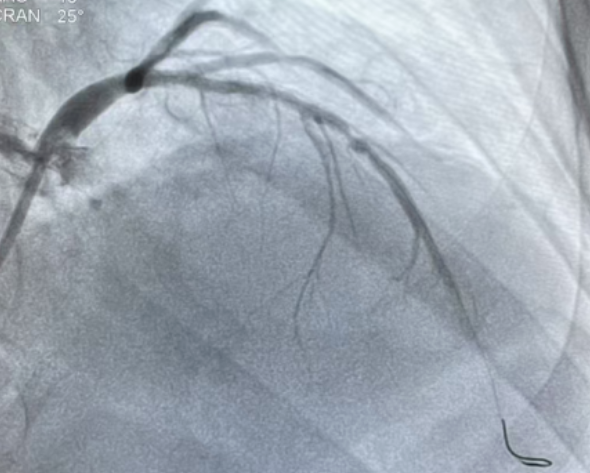

多管齐下解病痛:医院成功救治

复杂心血管疾病患者

2025年5月,莱佛士医院成功救治病情复杂的心血管疾病患者。医院采用多学科会诊模式,整合心血管、神经、内分泌等多学科资源,为患者制定个性化治疗方案,展现了医院在复杂疾病诊疗上的综合实力。